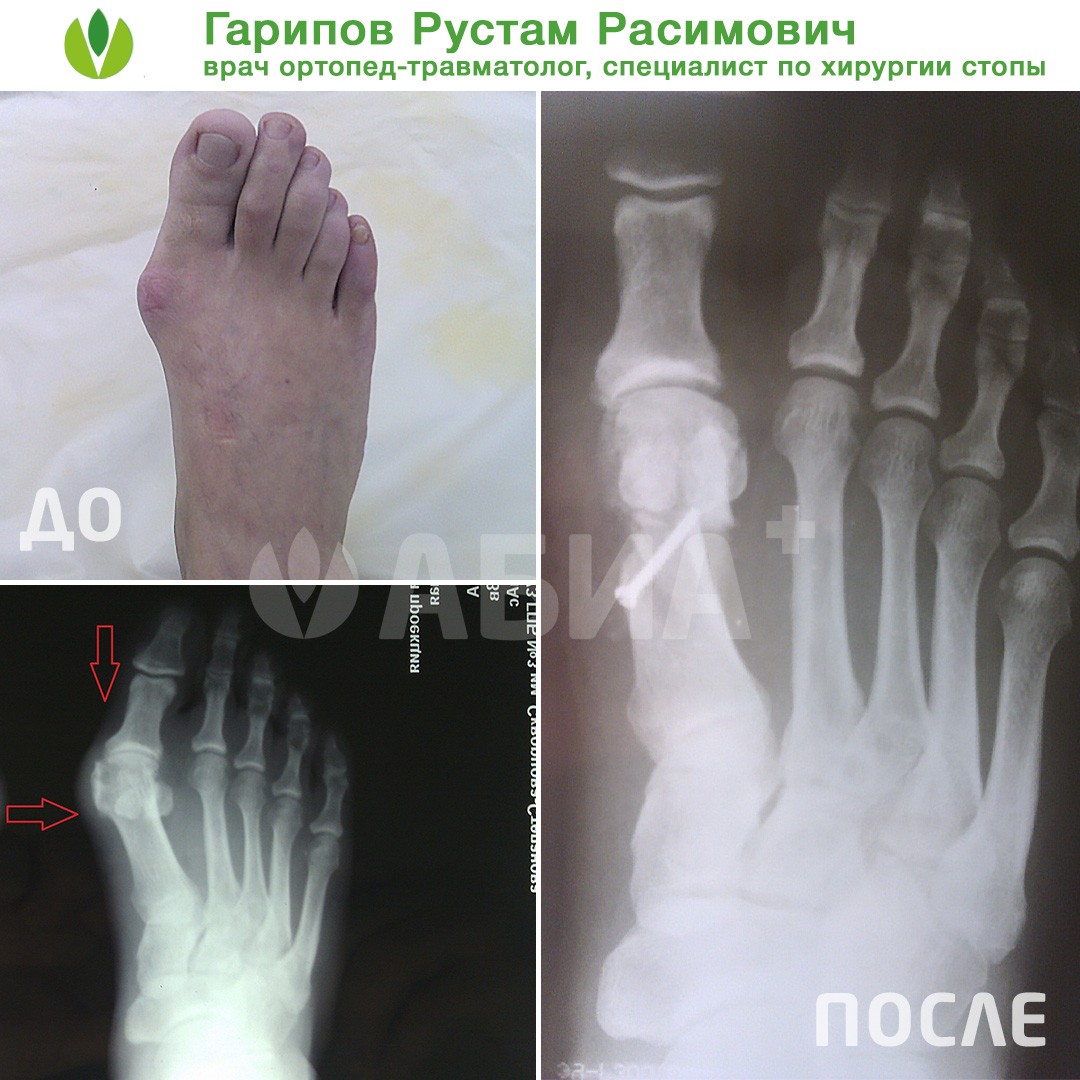

Одно из приоритетных направлений деятельности Рустама Расимовича - хирургия стопы по современным методикам Weil, Chevron, Scarf, Bosch, Akin и др.

Доктор выполняет операции при Hallux Valgus, Hallux Rigidus, Hallux Varus и других заболеваниях и деформациях стопы.